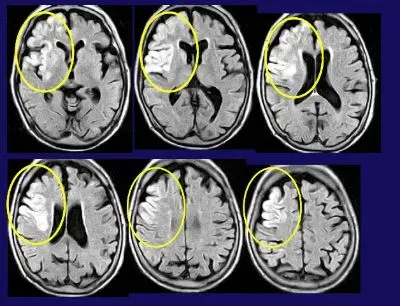

70歳のとき右足関節、80歳で左足関節の人工関節を受け、杖で歩くことができていた。3月31日に突然左片麻痺になって救急病院へ入院。初日は完全麻痺であったが、2日目少し動き出した。4月1日からリハビリを受け、留置膀胱カテーテルをしていた。4月4日にわれわれの病院へ転院。右前頭葉に大きな梗塞巣なる方でした。(図)

初日から400~500回起立・着席訓練を行った。するとみるみる回復していき、膀胱カテーテルも除去でき、1ヵ月後に杖歩行が自立し、10mを13秒で歩くことができ、外出も可能なまでに回復しました。病変は大きく、手は完全麻痺であったが、足の麻痺は比較的軽く、また早くリハビリを始められたために、歩行が自立したのでしょう。